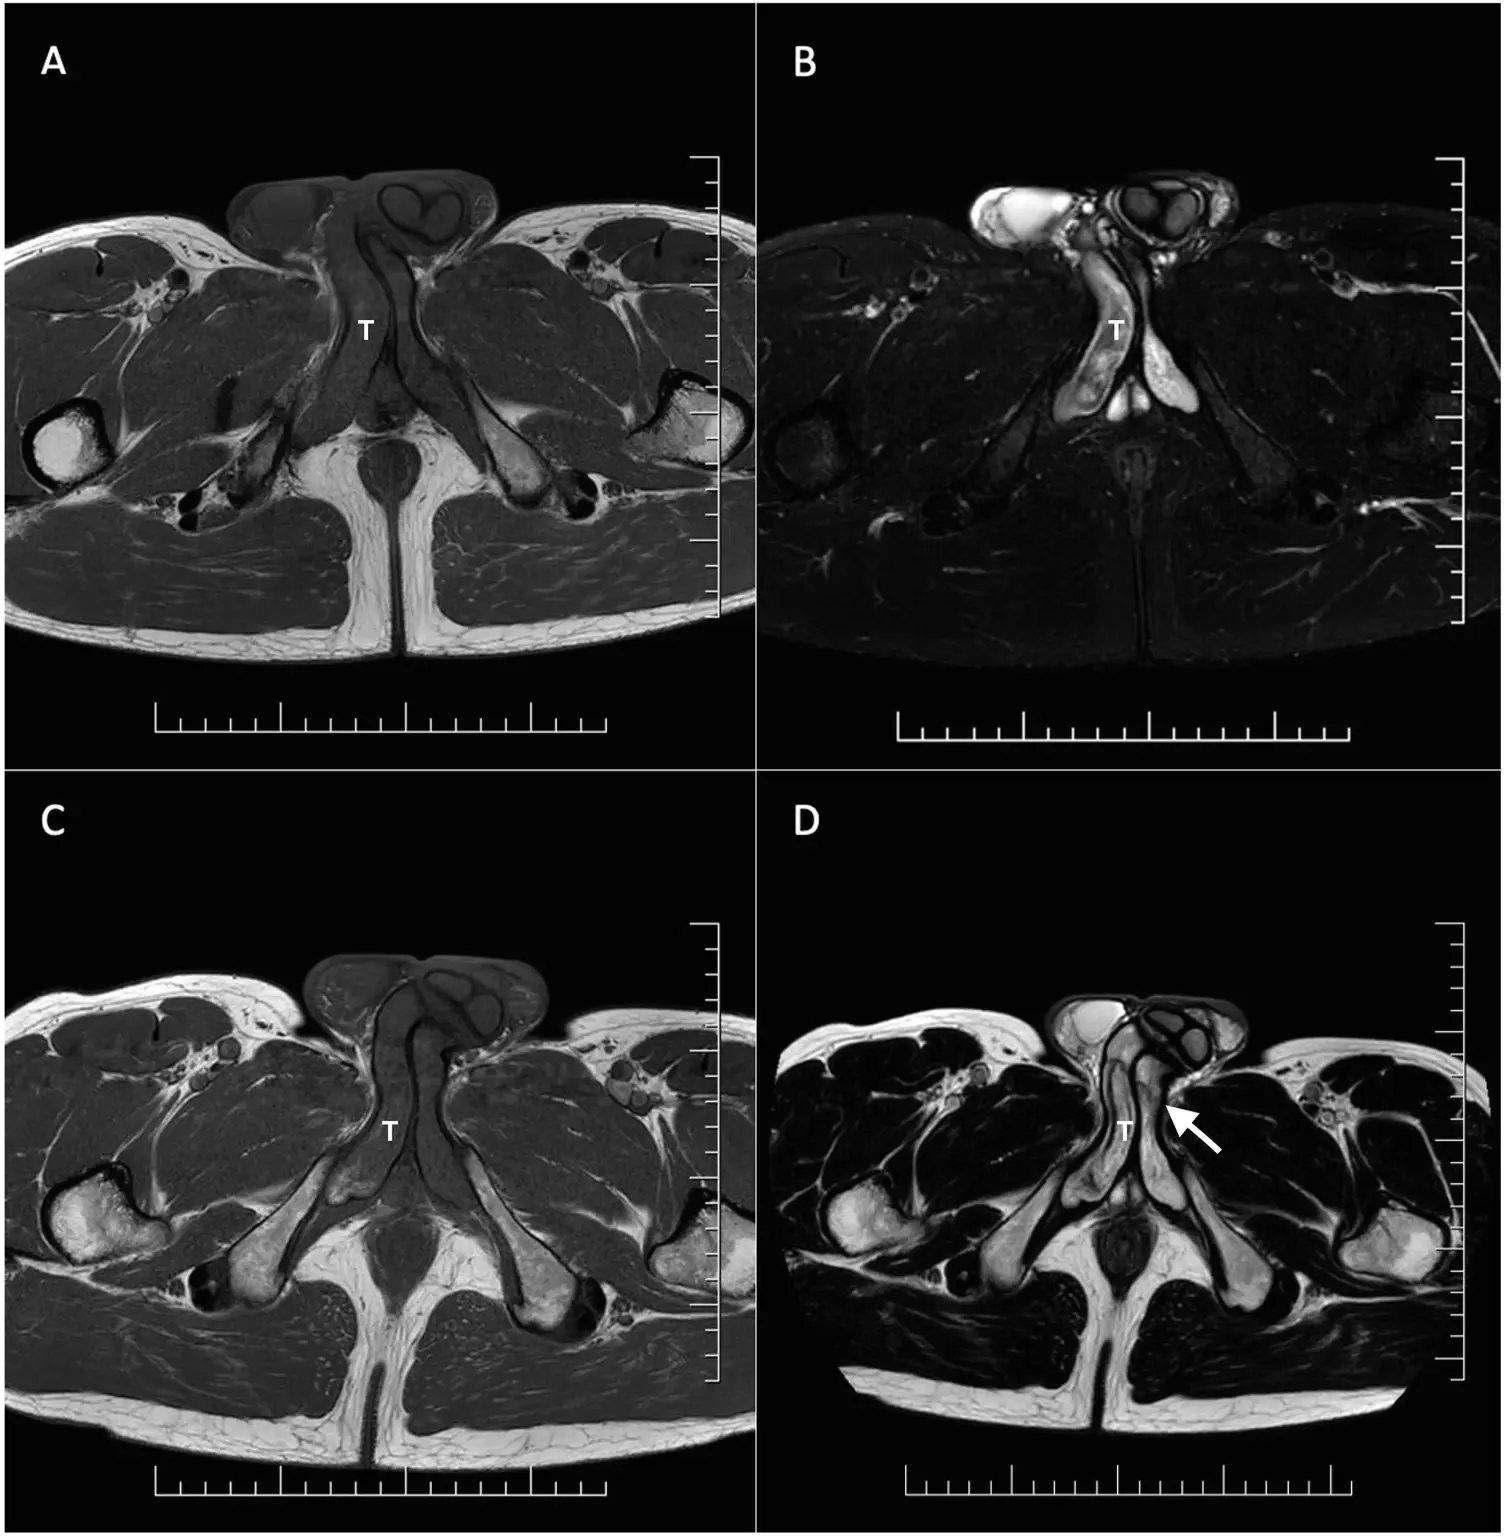

Μια μαγνητική τομογραφία από το νοσοκομείο Bory στη Μπρατισλάβα έδειξε ότι είχε θρόμβο αίματος πλάτους 18 χιλιοστών στα σηραγγώδη σώματα, που μπορούν να παρομοιαστούν με κυλίνδρους που γεμίζουν με αίμα και προκαλούν τη στύση

Του συνταγογράφησαν αντιπηκτικά και παυσίπονα και μια εβδομάδα αργότερα, ανέφερε ότι δεν πονούσε άλλο. Ωστόσο, ο θρόμβος παρέμεινε. Του χορηγήθηκε ενέσιμο φάρμακο για να μην μεγαλώσει ο θρόμβος και έξι μήνες αργότερα πράγματι μειώθηκε.

Τρία χρόνια αργότερα, ο θρόμβος του εξακολουθούσε να ανιχνεύεται αλλά δεν του προκαλούσε συμπτώματα. Ο θρόμβος στο σηραγγώδες σώμα είναι σπάνιος και έχει αναφερθεί μόνο 56 φορές, πιο συχνά σε άνδρες κάτω των 30 ετών.